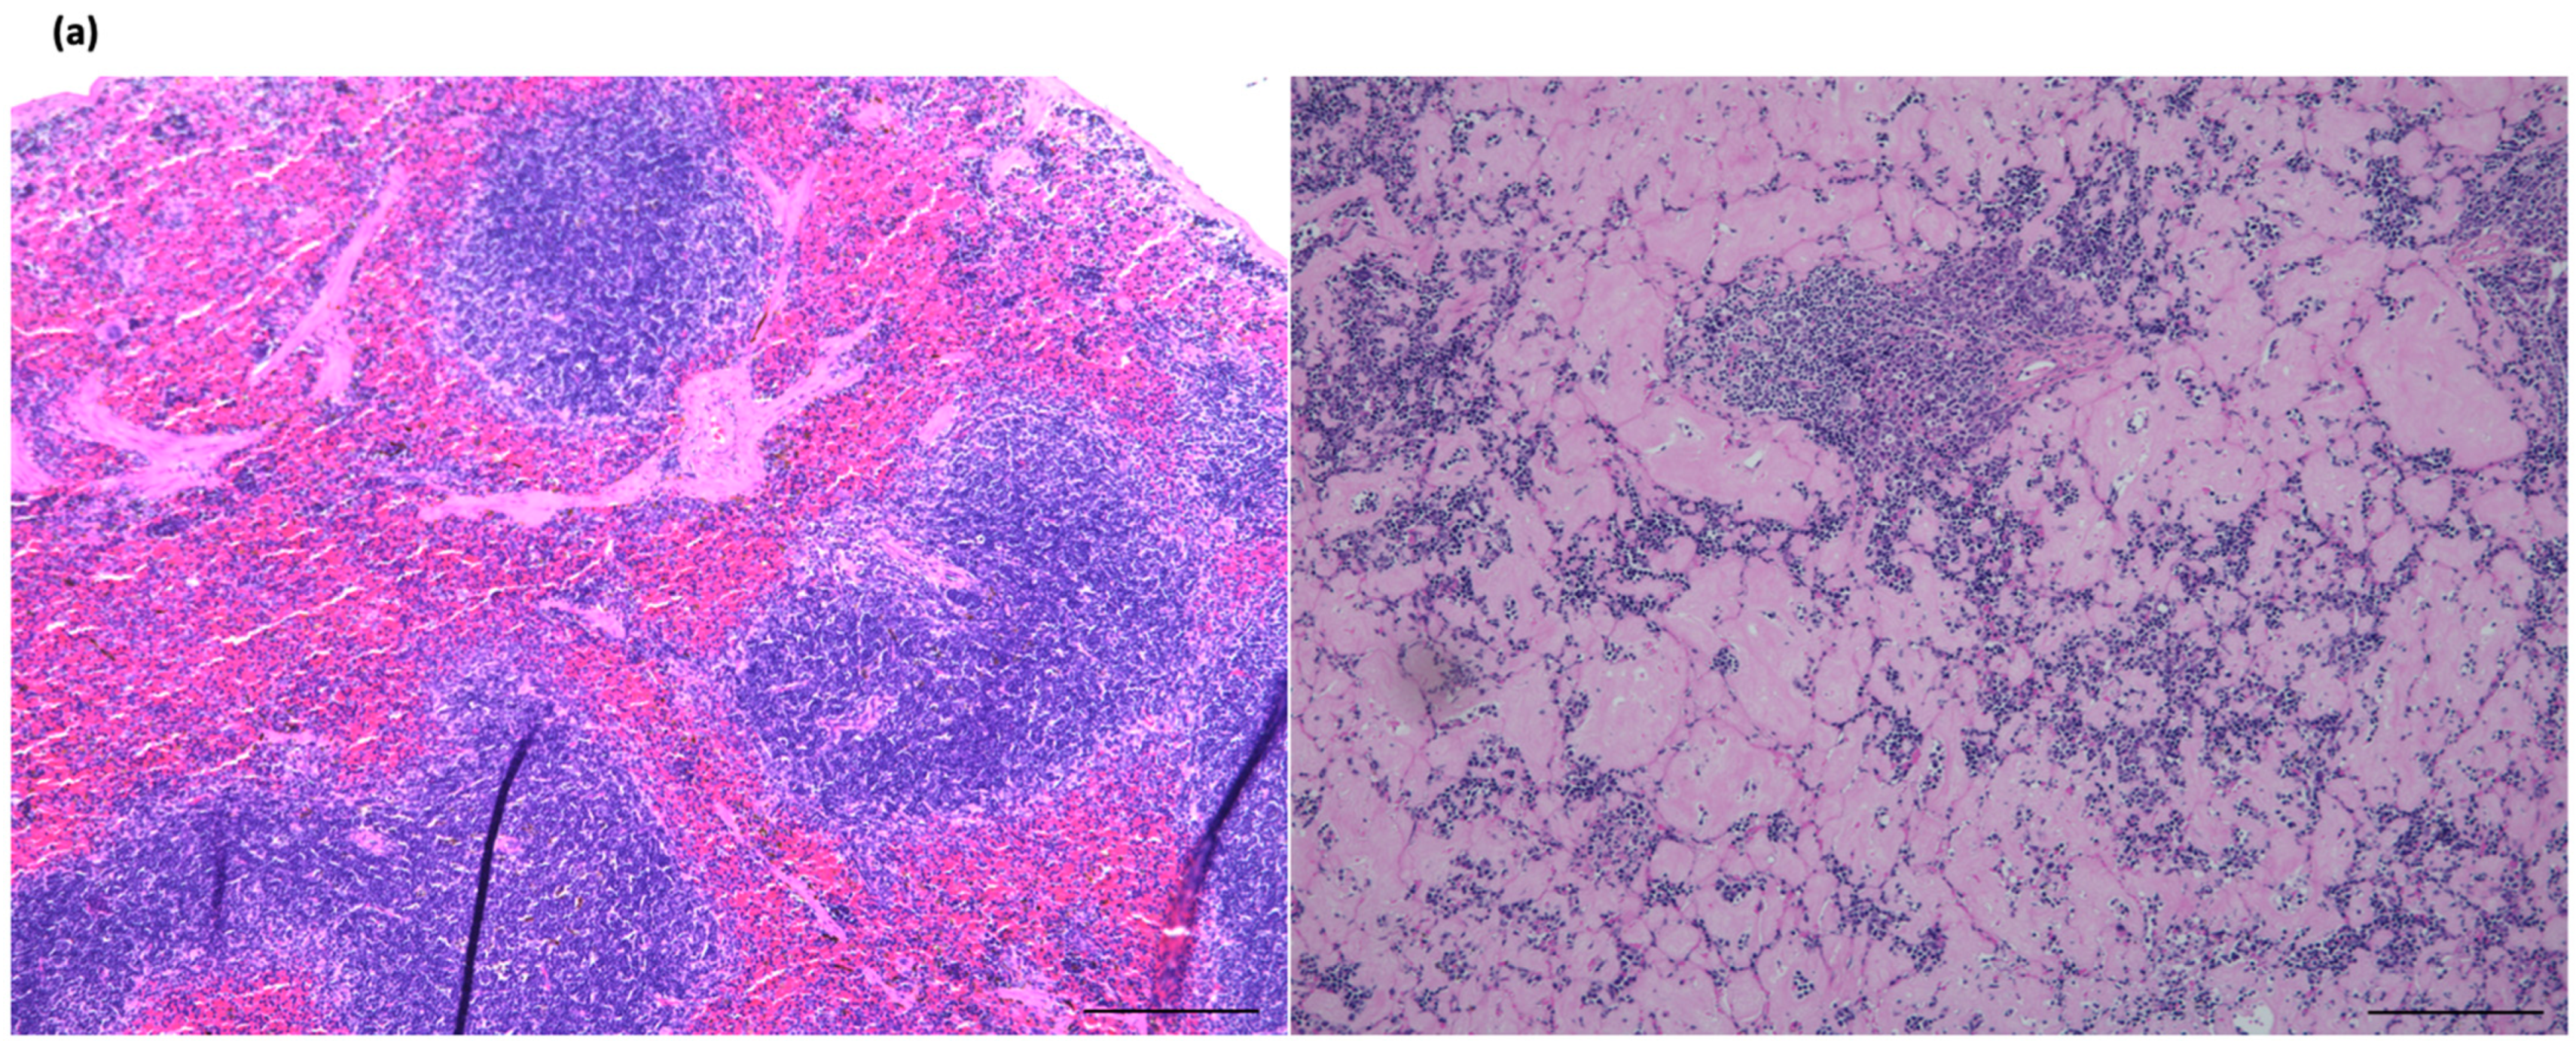

2.2. The Amyloid Deposition in the Spleen Was Rescued by the Deletion of IL-17A and Restored Lymph Follicle Formation, Not by IL-17F Deletion